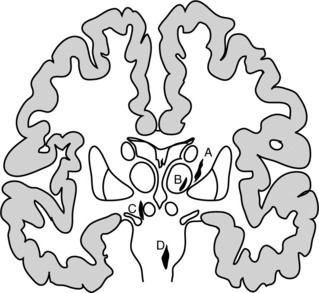

Lacunar Syndrome.: Lacunar infarcts are small infarcts of the end arteries found in the basal ganglia, internal capsule and pons. The lacunar infarcts have the characteristics of ischemic necrosis and the cysts are surrounded by astrocytic gliosis, or scarring of the support structures of the brain.44 These small, cystic spaces resulting from healed ischemic infarcts are common in individuals with hypertension or diabetes. A large majority are asymptomatic, but in about 20% of cases a stroke syndrome occurs with a slowly progressive (over 24 to 36 hours) dysfunction of the cells in the area of the lacune.64 The lacunar syndrome is representative of the area of infarct in which the lacunae are predominant often in the deep structures of the brain and have their effect often on white matter. If the posterior limb of the internal capsule is affected, a pure motor deficit may result; in the anterior limb of the internal capsule, weakness of the face and dysarthria may occur. If the posterolateral thalamus is affected there is a pure sensory stroke. When the lacunae occur predominantly in the pons, ataxia, clumsiness, and weakness may be seen. Fig. 32-11 shows the areas of predilection for lacunae to develop.

Figure 32-11 Usual sites of lacunar infarcts in the deep white matter. A, Internal capsule/putamen. B, Thalamus. C, Mesencephalon. D, Pons. (Reprinted from Pryse-Phillips W, Murray TJ: Essential neurology: a concise textbook, ed 4, New York, 1992, Medical Examination Publishing.) Medical Examination Publishing